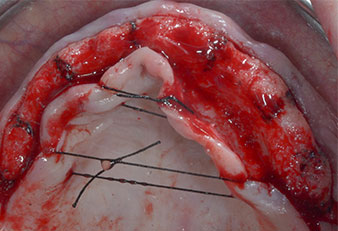

Trois ans après, le moment était venu pour elle de se doter d’une prothèse maxillaire du même type. Sur la base de la planification CBCT, l’élévation sinusale a été évitée grâce à la pose d'implants courts, et un gabarit chirurgical a été utilisé pour transférer les positions planifiées sur la crête alvéolaire (Figures 1 et 2).

Un insert piézoélectrique diamanté de forme effilée (Piezomed I1) a été utilisé pour marquer les positions implantaires et effectuer la préparation pilote (Fig. 3). On a pris soin de travailler selon un mouvement ascendant et descendant, à puissance réduite, irrigation complète et basse pression (moins de 300g). Ensuite, un insert pilote (Piezomed I2A/I2P) a été utilisé pour l’agrandissement initial de 2mm du diamètre des sites implantaires (Fig. 4), suivi d’un insert de 3mm (Fig. 5).